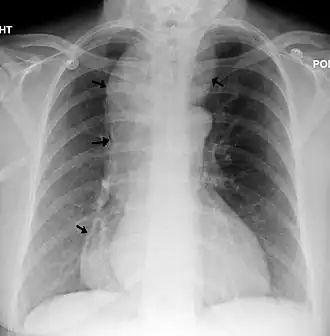

Radiographie thoracique d'un individu atteint d'achalasie. Les flèches indiquent les zones de dilatation œsophagienne extrême. | ||

L'achalasie, ou achalasie œsophagienne, est un trouble de la motricité du sphincter inférieur de l’œsophage. Celui-ci ne parvient pas à se détendre complètement, ce qui entraîne des vomissements et des régurgitations fréquentes, généralement une à deux heures après les repas[5],[4]. Si elle n'est pas traitée, la santé à long terme de l'individu sera compromise, conduisant au développement d'une dysphagie, d'une perte de poids et d'une aspiration chronique[5]. Il est très rare chez les enfants, en particulier les frères et sœurs[4]. La mortalité, en particulier chez les jeunes enfants, peut survenir[4].

L'achalasie provoque une dysphagie, qui entraîne des difficultés à manger, des vomissements fréquents après les repas et un éventuel arrêt respiratoire dû à une aspiration chronique[5],[6],[7]. Les symptômes peuvent se manifester dès l'âge de six semaines[7].